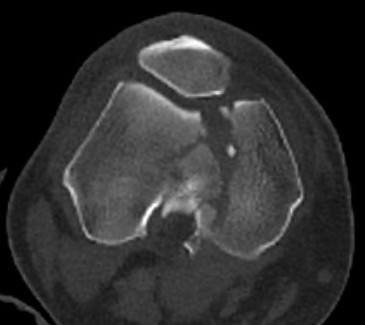

Type C: Complete articular

Xray / CT